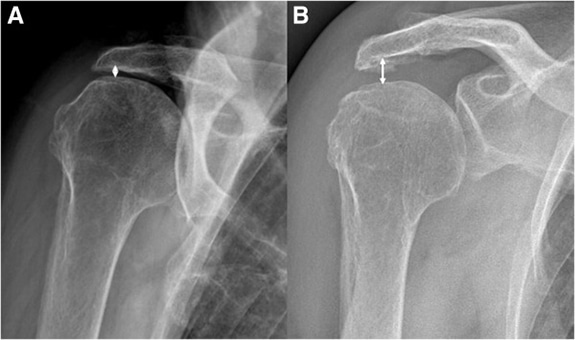

تستخدم هذه التقنية بالونًا قابلًا للتحلل الحيوي لخلق مساحة بين عظم الذراع العلوي ولوح الكتف، مما يقلل الألم ويحسن الحركة في حالات تمزق الكفة المدورة غير القابل للإصلاح.